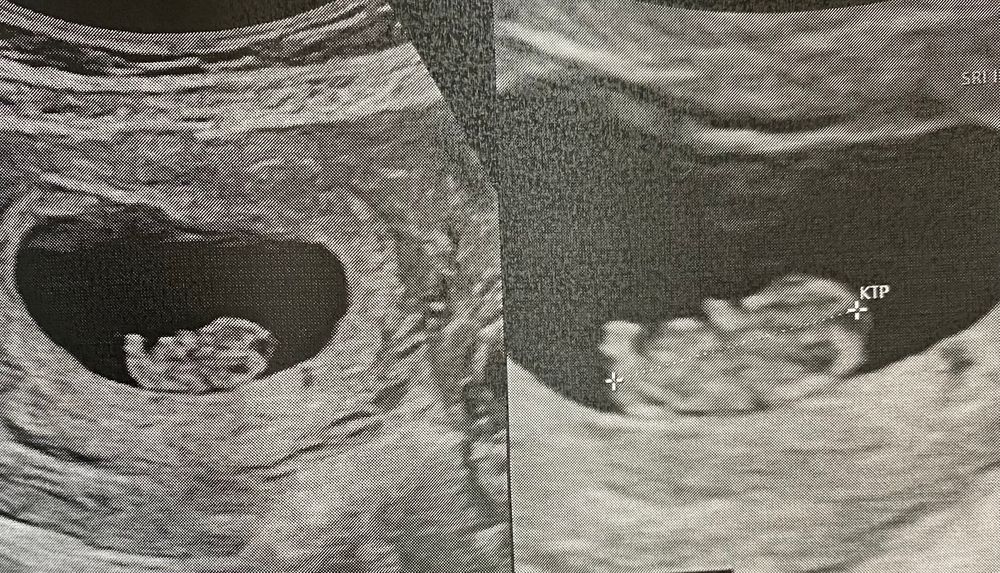

Узи 8 недель.На память для себя🌸

Уже прям такая себе ляля,ручки,ножки,пяточки,движения-прикольно)Кто же ты там,малышик,мальчик или девочка,так интересно)

ктр 20,5мм

Сб 175

жм-4мм

движения +

хорион по задней стенке.В прошлую беременность был по передней